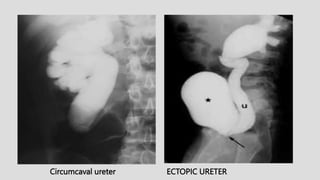

Circumcaval ureter ECTOPIC URETER